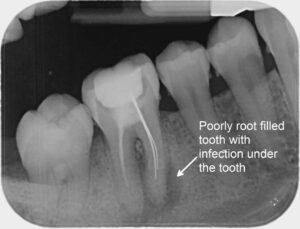

5.What Happens When a Root Canaled Tooth Fails

Signs of failure include:* Pain or sensitivity

* Darkening of the treated tooth

* Swelling or gum irritation

* Cracks or breakage

If ignored, infection can return, leading to more treatment or even extraction.